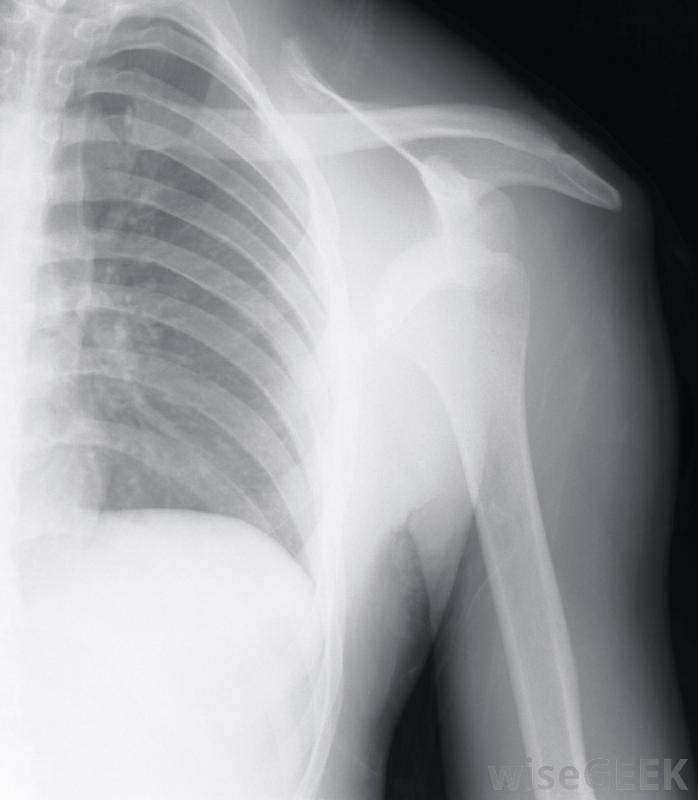

在进行肩峰成形术之前,外科医生可能需要做X光透视来观察肩关节的骨骼。运动员如果参加包括手臂和肩部头顶运动的体育活动,可能会患上撞击综合征肩部肌腱,尤其是肩袖,也可能是由于过度使用或重复性活动,如绘画或提举引起的。如果患者出现持续性疼痛,但用消炎药、休息或冰敷都无法缓解,外科医生可能需要进行肩峰成形术

如果患者出现持续性肩痛,他的外科医生可能想做一个肩峰成形术,他可能会先安排一系列的x光片来观察肩关节的骨骼。其他的检查,如核磁共振成像(MRI),也可能会被要求提供肩部有液体如果外科医生认为肩峰成形术对患者有利,则可将其作为开放手术或关节镜手术进行。